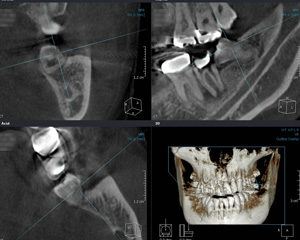

そこで、当院では、精密検査機器として「歯科専用のCT」を導入し、3次元撮影(水平・垂直・奥行)を行うことで、これまで十分に把握できなかった部分においても、より正確に診断できるようになりました。

歯科用CT歯科用CTで撮影すると、従来のレントゲンでは見れなかった歯の内部や骨の中などまで把握できるため、正確な診断・治療ができます。また、様々な角度から進行状態を3D画像で表示できるため、患者さんご自身にも病状を把握していただきながら治療を進めることができます。

歯ぐきの奥に埋まっている親知らずなどでさえも、3D画像によりあらゆる方向から状態を把握できます。神経の位置が明確にわかるようになったため、これまで以上に安全な抜歯が可能となりました。

歯の根の形態や数、曲がり具合や長さなどを立体的にとらえることができ、根管治療(歯の根の治療)においても非常に大きな役割を果たすようになりました。

歯周病の影響で歯を支える骨がどのくらい失われているか、また治療によってあごの骨がどれくらい再生しているか、などを3D画像で視覚的に確認することで、歯周病の進行具合や治療効果をより明確に把握できるようになりました。

手術前のCT撮影によって、下あごの神経の場所が把握できるため、インプラントをどのくらいの深さまで埋め込めるか、どの大きさの物を使えばよいかを把握できます。